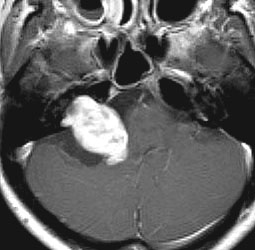

何も考えないで手術しなければならない時

聴神経腫瘍でまず手術が必要なのは巨大なものです。この4枚の写真は私が実際に手術をした患者さんのものです。脳幹部という脳の最も大切なところが腫瘍によって圧迫されて変形しているのが特徴です。右上のものはのう胞性腫瘍なので大きさの割に手術のリスクは高くありませんが,左上のものは実質性で出血性のものですごくリスクが高い手術でした。左下のものは普通のリスク。右下のものは超高難易度のものです。